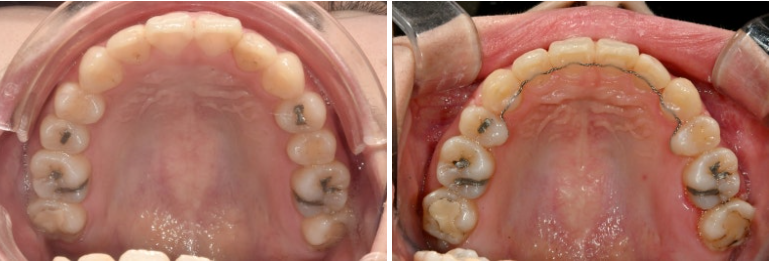

거미스마일도 심한 편이었으며 돌출과 거미스마일 해소를 위해 작은어금니 4개를 발치하고 치료에 들어갔습니다.

치료방법은 인비절라인 선택하셨고 첫 세트 장치는 85개가 나왔습니다.

발치교정에서 거미스마일 개선을 위해서는 교정용 나사에 환자분이 뺏다꼈다 하는 고무줄 처방이 함께 들어갑니다.

25년 5월까지 1년 10개월간 85개 장치를 모두 낀 후 모습입니다.

25.05

중심선은 잘 맞으며

앞니사이 공간이 조금 남아있습니다.

어금니 교합은 좋은 편

미세하게 남은 발치공간을 없애기 위해 추가장치 제작에 들어갑니다.

추가장치 갯수는 11개이며 25년 6월부터 9월까지 꼈습니다.

그리고 이번달 드디어 치료를 마무리 했습니다.